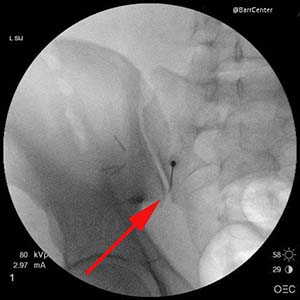

You will receive a local anesthetic before a small spinal needle is inserted under fluoroscopic guidance into the SI joint. The procedure takes approximately 15 minutes. The arrow shows the needle within the sacroiliac joint. Once the needle is securely positioned into the joint a small amount of x-ray contrast dye will be injected confirming proper needle placement, then a mixture of steroid and lidocaine will be injected. The joint will numb up within just a few minutes and you will notice the effects of the steroid within several days.

You will receive a local anesthetic before a small spinal needle is inserted under fluoroscopic guidance into the SI joint. The procedure takes approximately 15 minutes. The arrow shows the needle within the sacroiliac joint. Once the needle is securely positioned into the joint a small amount of x-ray contrast dye will be injected confirming proper needle placement, then a mixture of steroid and lidocaine will be injected. The joint will numb up within just a few minutes and you will notice the effects of the steroid within several days.

X-ray image of an actual left sacroiliac joint injection.